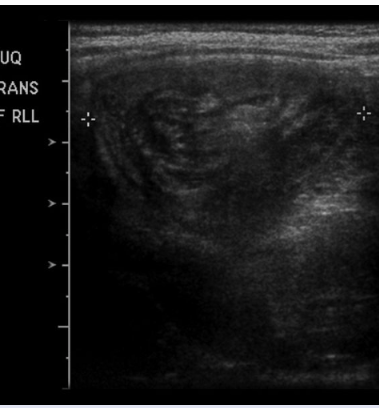

A 2-year-old boy is brought to the emergency department (ED) episodic abdominal pain, blood in his diaper, and a recent diarrheal illness. A diagnosis is made using ultrasonography.

Ultrasonography of the abdomen in patients with intussusception classically shows a “bullseye” or “target” sign, which represents the infolding of the small intestine.